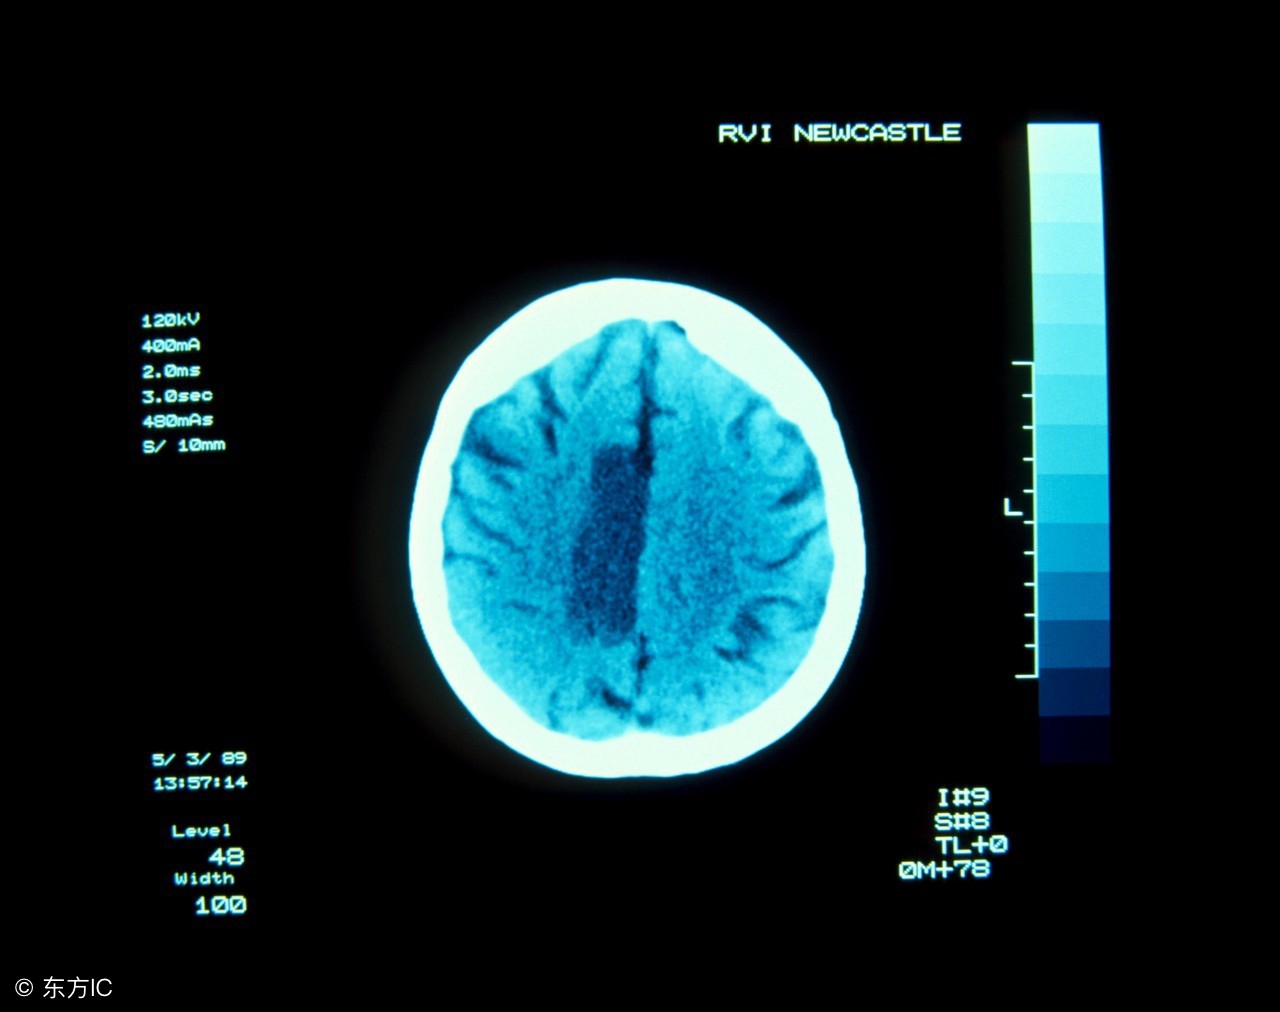

(3)脑CT检查显示脑梗塞病灶的大小和部位准确率66.5%~89.2%,显示初期脑出血的准确率100%。因此,早期CT检查有助于鉴别诊断,排除脑出血等病变。这是十分重要的,发病早期脑出血与脑血栓形成的治疗有截然不同的地方。当脑梗塞发病在24小时内,或梗塞灶小于8毫米,或病变在脑干和小脑处,脑CT检查往往不能提供正确诊断。必要时应在短期内复查,以免延误治疗。